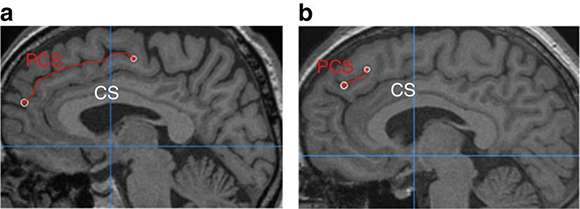

A certain fold only appears in thirty to sixty percent of the population and may appear in the left or right parts of the brain, or in both. The fold, called the Paracingulate Sulcus, is indicated in red in the image | From Garrison et al., Nature communications 2015

Yet, not all brains share the exact same structure. One notable difference is a particular sulcus found in only thirty to sixty percent of the population. Known as the Paracingulate Sulcus, this fold is part of the anterior cingulate cortex. It develops in the later stages of development and can form asymmetrically, often found predominantly in the left hemisphere.